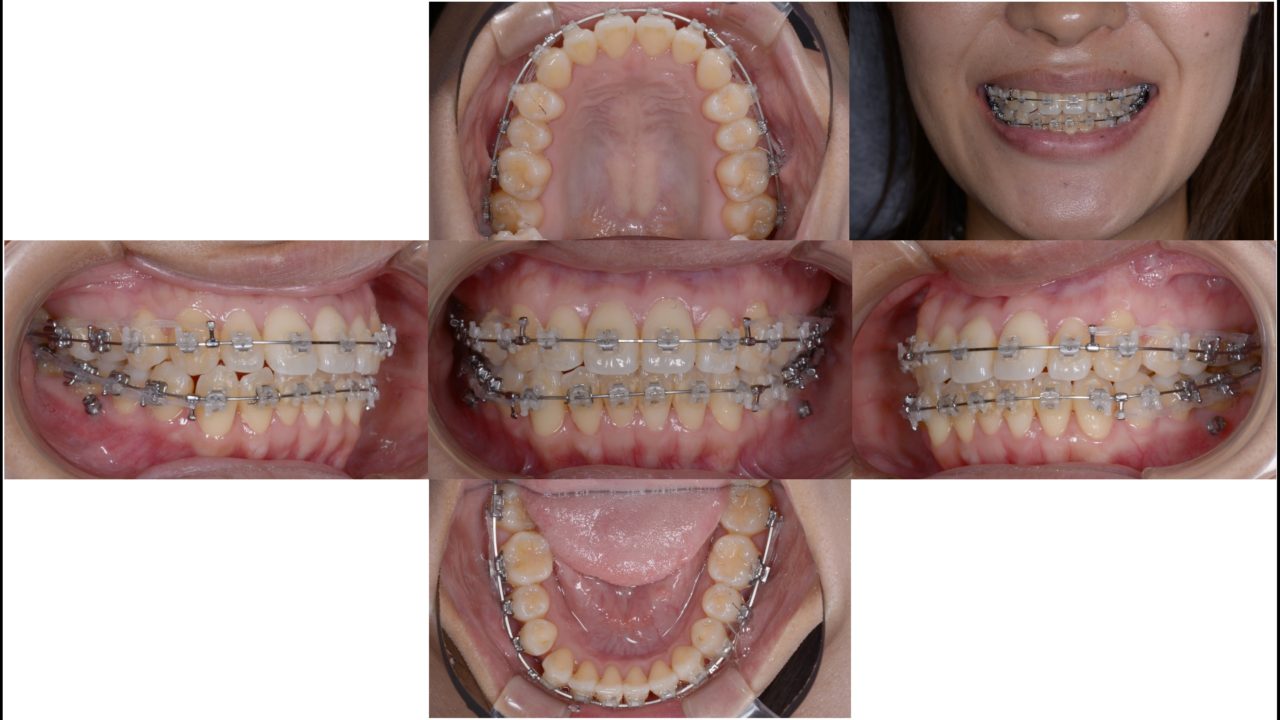

矯正治療開始 2019.6.28

マルチブラケットを上下顎に装着しました。歯は抜いていません。凸凹を治すためにマリガンオーバーレイアーチで側方拡大を行います。

開始5か月 2019.11.19

予定通り、5か月でほぼ前歯の凸凹は治りました。しかし、前歯がきれいになると口元をもっと引っ込めたいという希望が出てきました。治療計画を一部変更して、矯正用アンカースクリューを使い、上下顎の歯すべてを後方へ移動させる計画を入れました。